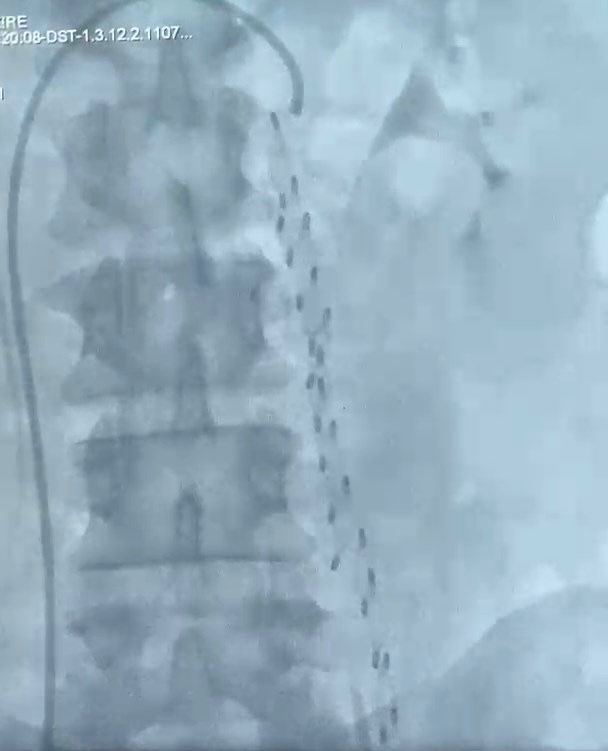

Siirt Eğitim ve Araştırma Hastanesi'nde, kadınlarda kasık varislerine yol açan "Pelvik Konjesyon Sendromu" için ilk kez bir operasyon gerçekleştirildi. Bu sendrom, kadınların karın alt bölgesinde, özellikle pelvis ve yumurtalıklar çevresinde varislerin oluşması ile biliniyor. Hastalar genellikle karın ağrıları, idrarda gizli kanama ve genital bölge ile kasıklarda belirgin varisler ile karşı karşıya kalıyor.

Yaklaşık her 10 kadından birinde görülen bu sendrom, genellikle 20 ila 45 yaş arasındaki kadınlarda daha sık rastlanıyor. Ayrıca, doğum sayısının artmasıyla sendromun görülme olasılığı da yükseliyor. Hafif şikayetler için ağrı kesici ve semptomatik ilaçlar faydalı olabiliyor. Ancak açık cerrahi tedavi, risk ve komplikasyonlar nedeniyle pek önerilmiyor. Bunun yerine, yumurtalıklara ve çevre genital organlara giden genişlemiş varislerin ameliyatsız damar içi yolla tıkanmasına dayanan embolizasyon yöntemi, güvenli ve etkili bir çözüm sunuyor.

Operasyonu gerçekleştiren Op. Dr. Kadir Çekirdekoğlu, süreci şöyle anlattı: "Siirt Eğitim ve Araştırma Hastanesi'nde, anjiyo ünitesinde lokal anestezi altında hastanın kasık bölgesinden giriş yaparak kan kaçağı olan damara tıkaç malzemesi yerleştirdik. Bu sayede hastamızı sağlığına kavuşturduk. Hastanemizde ilk kez yapılan bu işlem sayesinde artık hastalarımızın tedavilerini Siirt'te yapabiliyoruz ve dış merkezlere sevklerin önüne geçiyoruz."